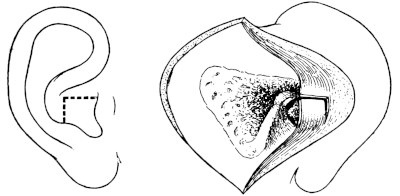

| 209. | Eustachian Catheter | 365 |

| 210. | Passing the Eustachian Catheter | 365 |

| 211. | Passing the Eustachian Catheter | 365 |

| 212. | Passing the Eustachian Catheter | 366 |

| 213. | Passing the Eustachian Catheter | 366 |